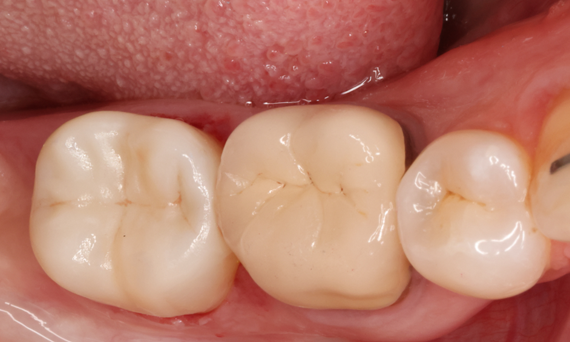

Deuxième molaire mandibulaire droite en 90 minutes

Un onlay CEREC Tessera

Une patiente de 20 ans a subi un traitement endodontique de sa 2e molaire mandibulaire. Un onlay a été fabriqué en consultation à partir de la nouvelle céramique à haute résistance CEREC Tessera ALD.

Avant : Scénario clinique préopératoire après le traitement endodontique.

Après : 1 mois après le collage de l’onlay CEREC Tessera.